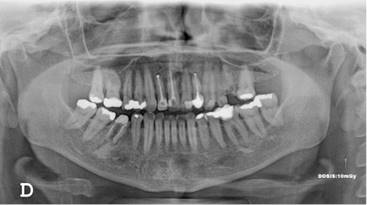

Los resultados mostraron que en el 48 % de la población se encontró algún hallazgo relacionado con la pulpa dental, con frecuencias similares entre hombres y mujeres, siendo el tratamiento endodóntico el más frecuentemente encontrado (Tabla 1, Fig. 1). El rango del número de endodoncias por radiografía fue de 1 a 18. El 86,4 % de las radiografías presentaron de 1-5 endodoncias, 11,4 % de 6-10 y el 2,2 % de 11-18. La presencia de zona radiolúcida periapical seguida por la reabsorción (Fig. 2), fueron los siguientes hallazgos más frecuentes. (Tabla 1)

Los otros hallazgos analizados (Fig. 3) se presentaron en muy baja frecuencia. Para ninguno de los casos, se encontraron diferencias estadísticamente significativas entre hombres y mujeres.

Un total de 1.590 dientes que tenían tratamiento endodóntico, se clasificaron según su estado: el 44,9 % de los dientes presentaron endodoncias en buen estado, mientras que aproximadamente la mitad de ellos se encontraron subobturados (52,7 %) y el 2,5 % sobreobturados. El 95.6 % de los dientes tratados endodónticamente, presentaban algún tipo de restauración.

Cuando se analizó la frecuencia de tratamientos endodónticos por el tipo de diente, se encontró mayor frecuencia en dientes del maxilar superior (69,1 %), siendo los más tratados los primeros molares superiores e inferiores en ambos maxilares y los centrales superiores (Gráficos 1 y 2).

El análisis de la presencia de zona radiolúcida periapical, mostró que del total de dientes en boca, el 0,6 % de los que no tenían endodoncia tienen lesiones apicales mientras que el 11% de los que tienen endodoncia se asocian con una lesión apical (p<0,000000). Sin embargo el cálculo del OR (OR=0,047) mostró una relación negativa de riesgo entre tener una endodoncia y presentar lesión apical. De los 389 dientes en los que se observó el hallazgo compatible con radiolucidez periapical, 171 (44 %) tenían tratamiento endodóntico, de los cuales 66 % estaban subobturados, 31% bien obturados y 3% sobreobturados.